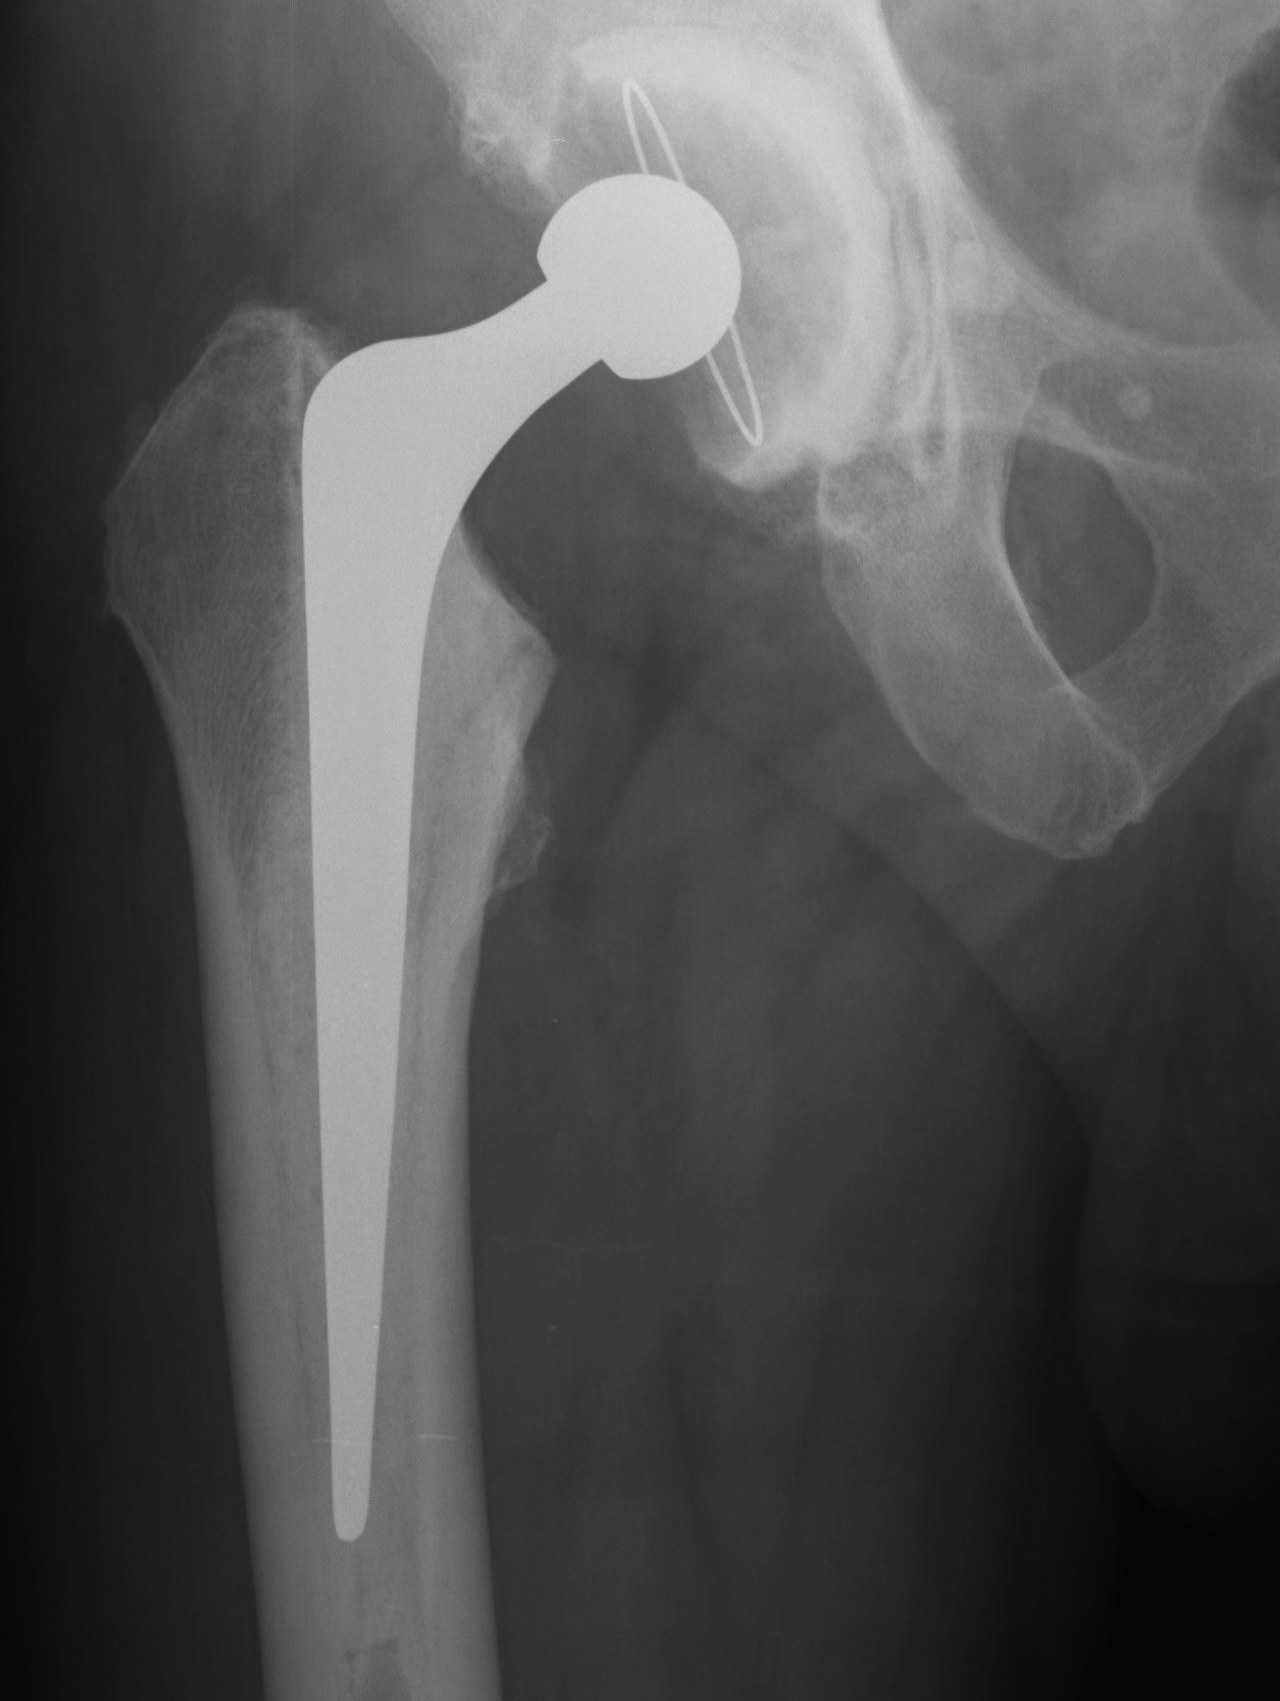

Extended Trochanteric osteotomy

Concept

Osteotomy lateral 1/3 to 1/2 of trochanter / femur

- posterior to anterior longitudinal cut

- short distal transverse cut

- levers / hinges open anteriorly

- maintains anterior vasculature / muscle attachment

Fixation

- 3 x cerclage cables, tension

- protect sciatic nerve

- submuscular

Results

98 – 100% union rate by 6/12